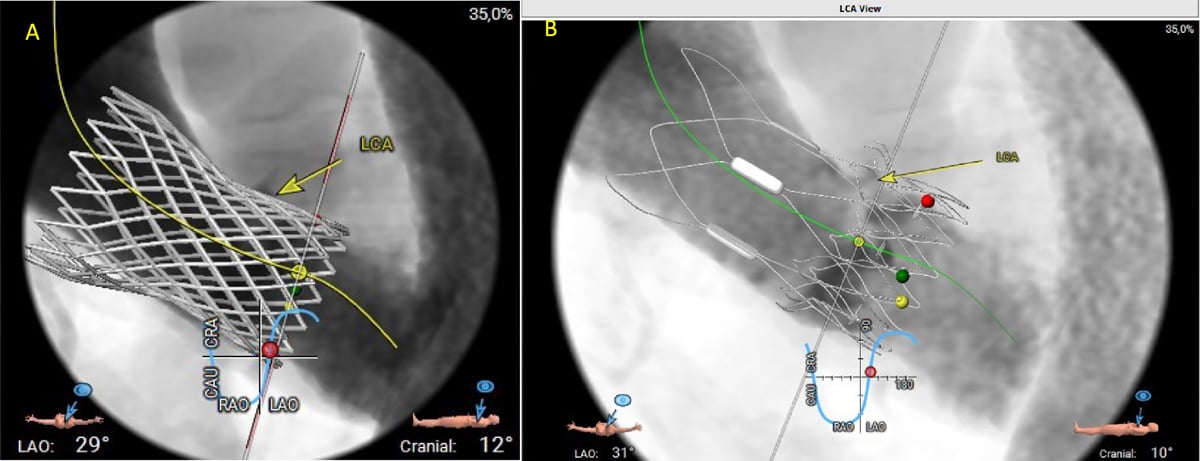

Aufgrund der Verkalkung im LVOT und des geringen LVOT Diameters kam eine ballonexpandierbare Klappe nicht in Frage. Wir befürchteten, dass bei den beiden zu diesem Zeitpunkt (November 2024) zur Verfügung stehenden selbstexpandierenden supraannulären Klappen ein hohes Risiko einer Obstruktion der linken Koronararterie aufgrund des schmalen SOV/STJ und des kompakten Stentgerüsts (Abbildung 7A) oder aufgrund der räumlichen Nähe der oberen Krone zum Ostium der linken Koronararterie (Abbildung 7B), bestehen würde. Daher entschieden wir uns für eine transfemorale TAVI mit der 25 mm Abbott Navitor Vision selbstexpandierenden intra-annulären Prothese.

Abbildung 7: Projektionen von 2 Typen von Transkatheter-Aortenklappen

In der Prozedurplanung wurde die Implantation einer ballonexpandierbaren THV aufgrund des Risikos einer Annulusruptur abgelehnt. Die virtuelle Implantation einer Katheterklappe in den rekonstruierten CT-Datensatz ergab ein potenzielles Risiko für eine Obstruktion der linken Koronararterie aufgrund der Dimensionen und des Designs des Medtronic Evolut THV Prothesenrahmens sowie einer Protrusion der oberen Krone der Boston Acurate THV, die nicht mehr im Handel erhältlich ist, in das LCA-Ostium.